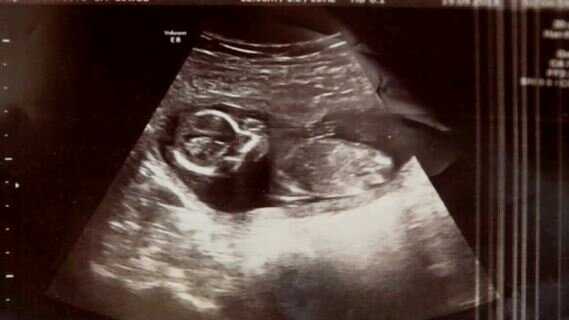

O 10 dní později, v nemocnici, měla Michelle poslední ultrazvuk před operací. Pak doktor objevil něco šokujícího. Slyšel ... tlukot srdce! Žena, navzdory potratu a polykání prášku na potrat, byla těhotná!

Ukázalo se, že předtím čekala dvojčata a bohužel jedno dítě zemřelo, když potratila. Nikdo neví, jak přežilo druhé dítě, ale jedno je jisté. Rodiče měli opravdu štěstí!